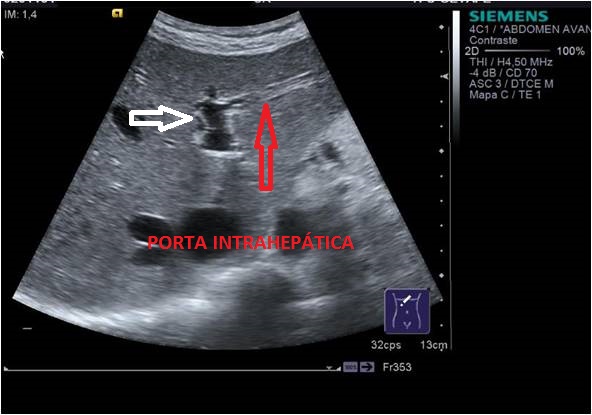

Este corte lo vamos a realizar axial al cuerpo, situando nuestro transductor un poco por encima de donde buscamos el Páncreas y en línea media y le vamos a pedir a la/el Paciente que coja aire y que lo aguante, tenemos que conseguir algo muy parecido a esto:

Veremos una porción de la Porta (flecha blanca), en el Lóbulo Hepático Izquierdo y una, dos o más ramas que salen de ella hacia la izquierda del paciente (flecha roja), ocupando el LHI.

Las Ramas Izquierdas tienen aspecto de tenedor con varias púas, 2 normalmente, pero a veces más, una más superficial, otra más profunda y es difícil sacarlas en un mismo plano, a veces hay que realizar una foto para cada rama. En la foto de arriba vemos que sacamos la superficial y en la foto de abajo, la profunda.

Ecográficamente tiene un aspecto anecoico y alargado sobre el lóbulo hepático izquierdo, pero la bordea, tanto a la Porta como a las ramas izquierdas de ésta, un perfil hiperecogénico que no vamos a encontrar por ejemplo en las Venas Suprahepáticas. Este perfilado hiperecogénico se debe al colágeno que rodea dicho vaso.